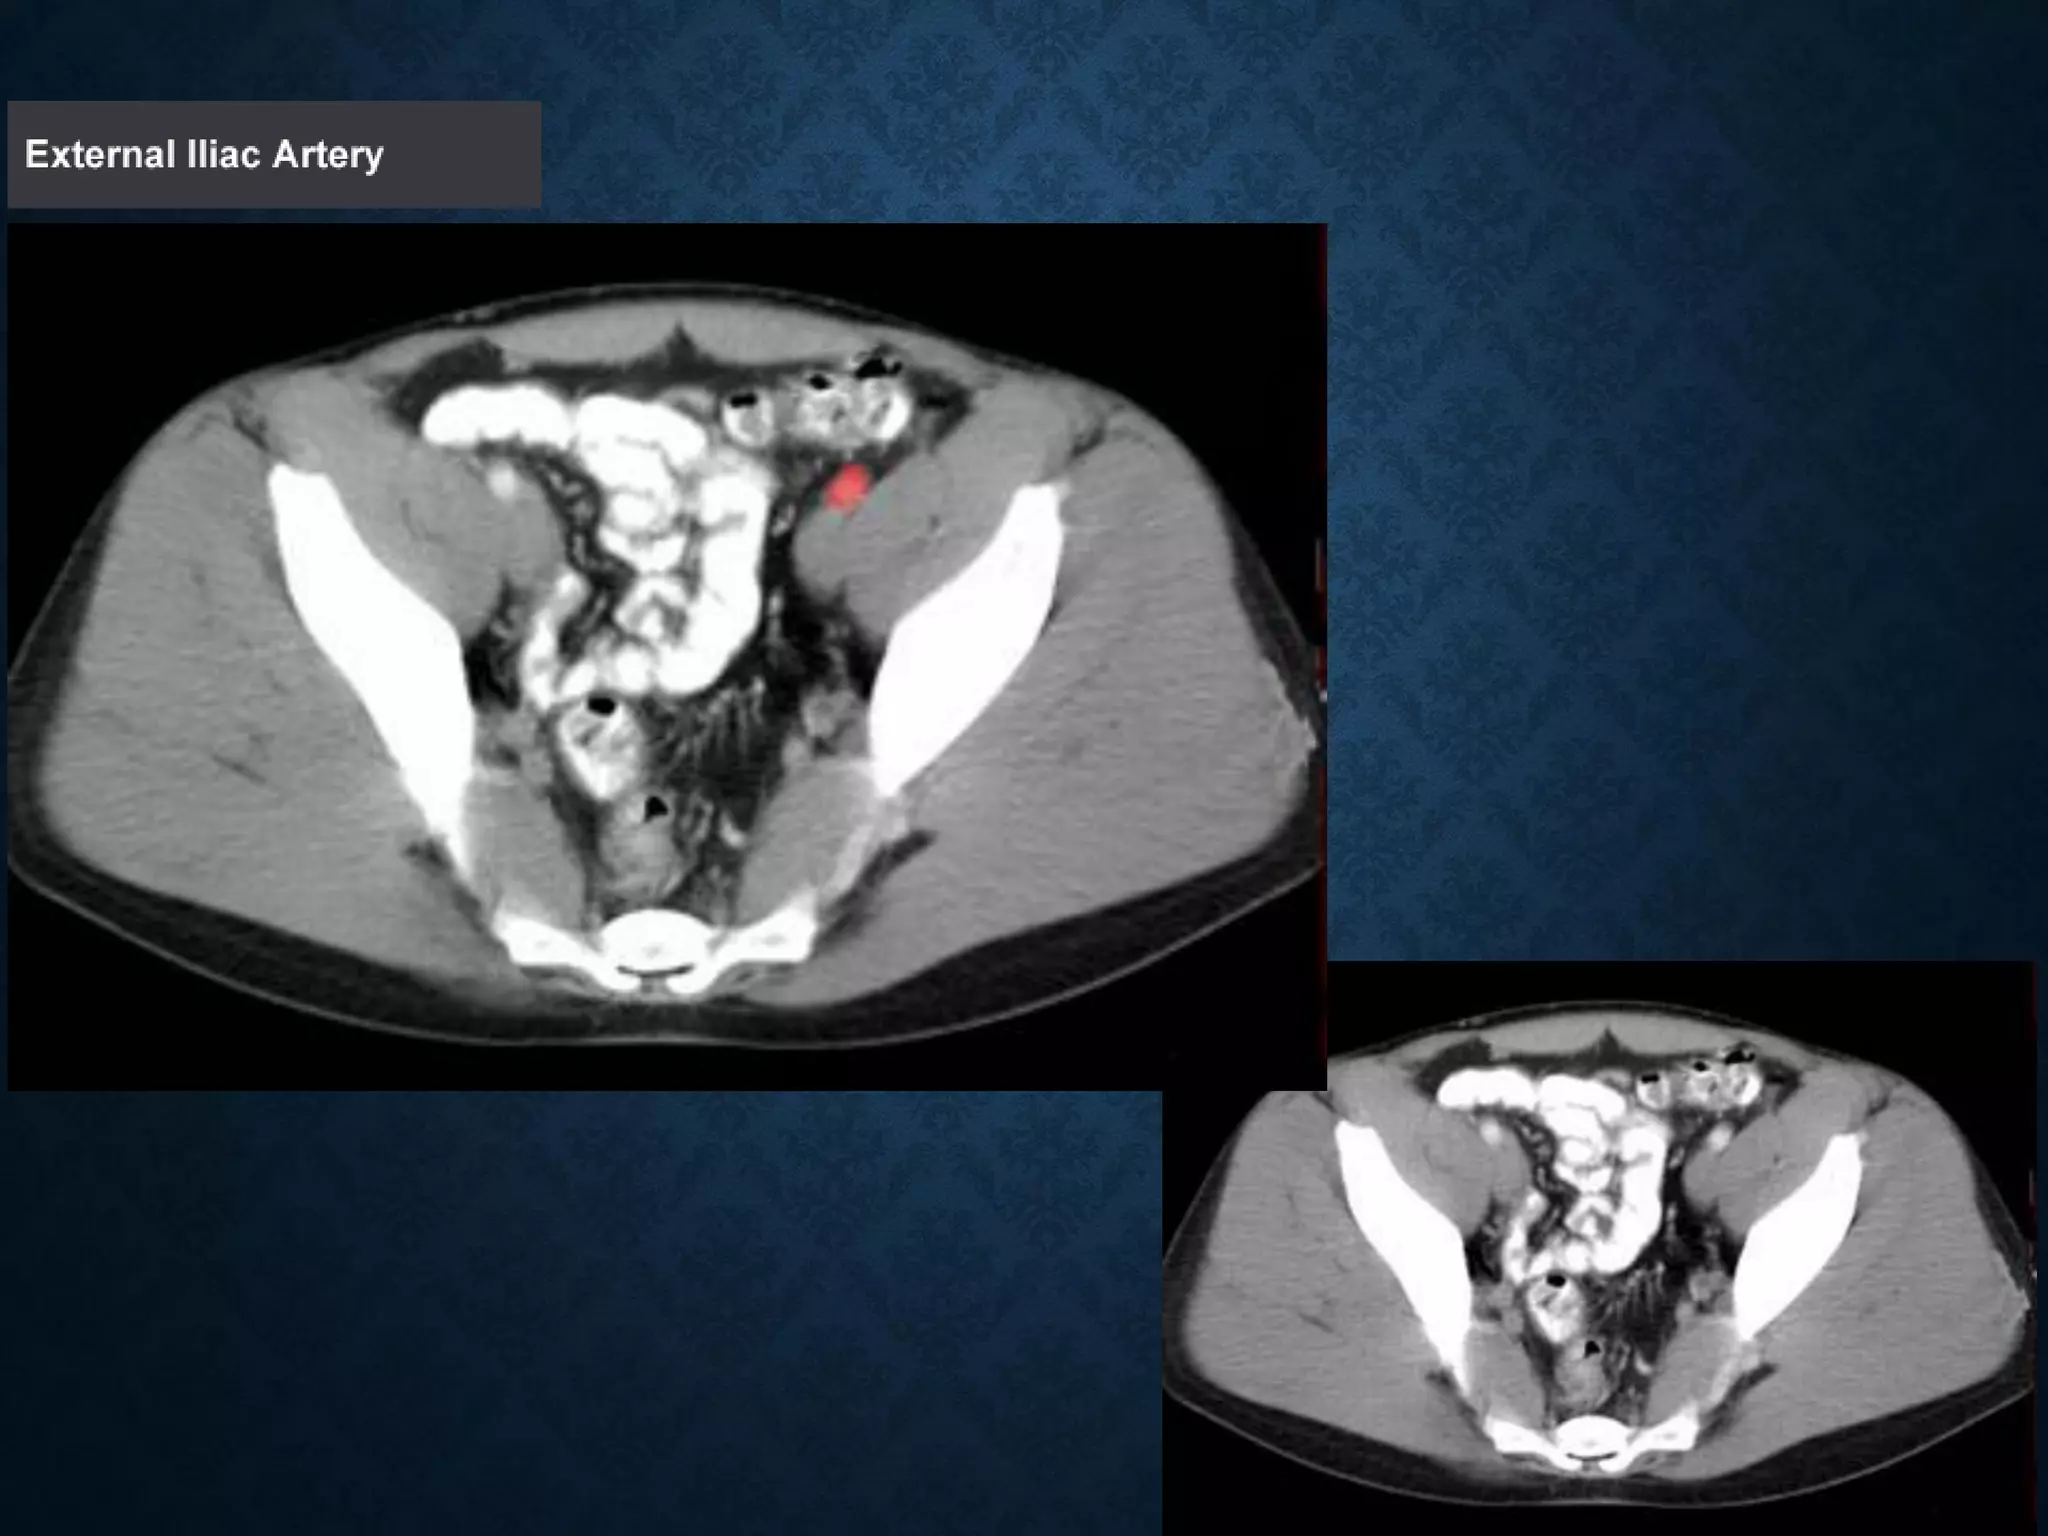

Identify the following structures in the body CT to the right. To view the location of the structure in the image click on

the label at the left and the structure will be indicated in the image. Abdominal CT scans typically begin just above

the diaphragm, so the first slice you see is of the lower chest.

Identify the followingstructures in the body CT to the right. To view the location of the structure in the image click on the label at the left and the structure will be indicated in the image. Abdominal CT scans typically begin just above the diaphragm, so the first slice you see is of the lower chest.

ABDOMINAL AORTA origin: Continuationof descending thoracic aorta at T12 • course: descends anterior and slightly to the left of the lumbar vertebral bodies. •Bifurcation of aorta:L4 • Note that the bifurcation (union) of the inferior vena cava is at L5and therefore below that of the bifurcation of the aorta)